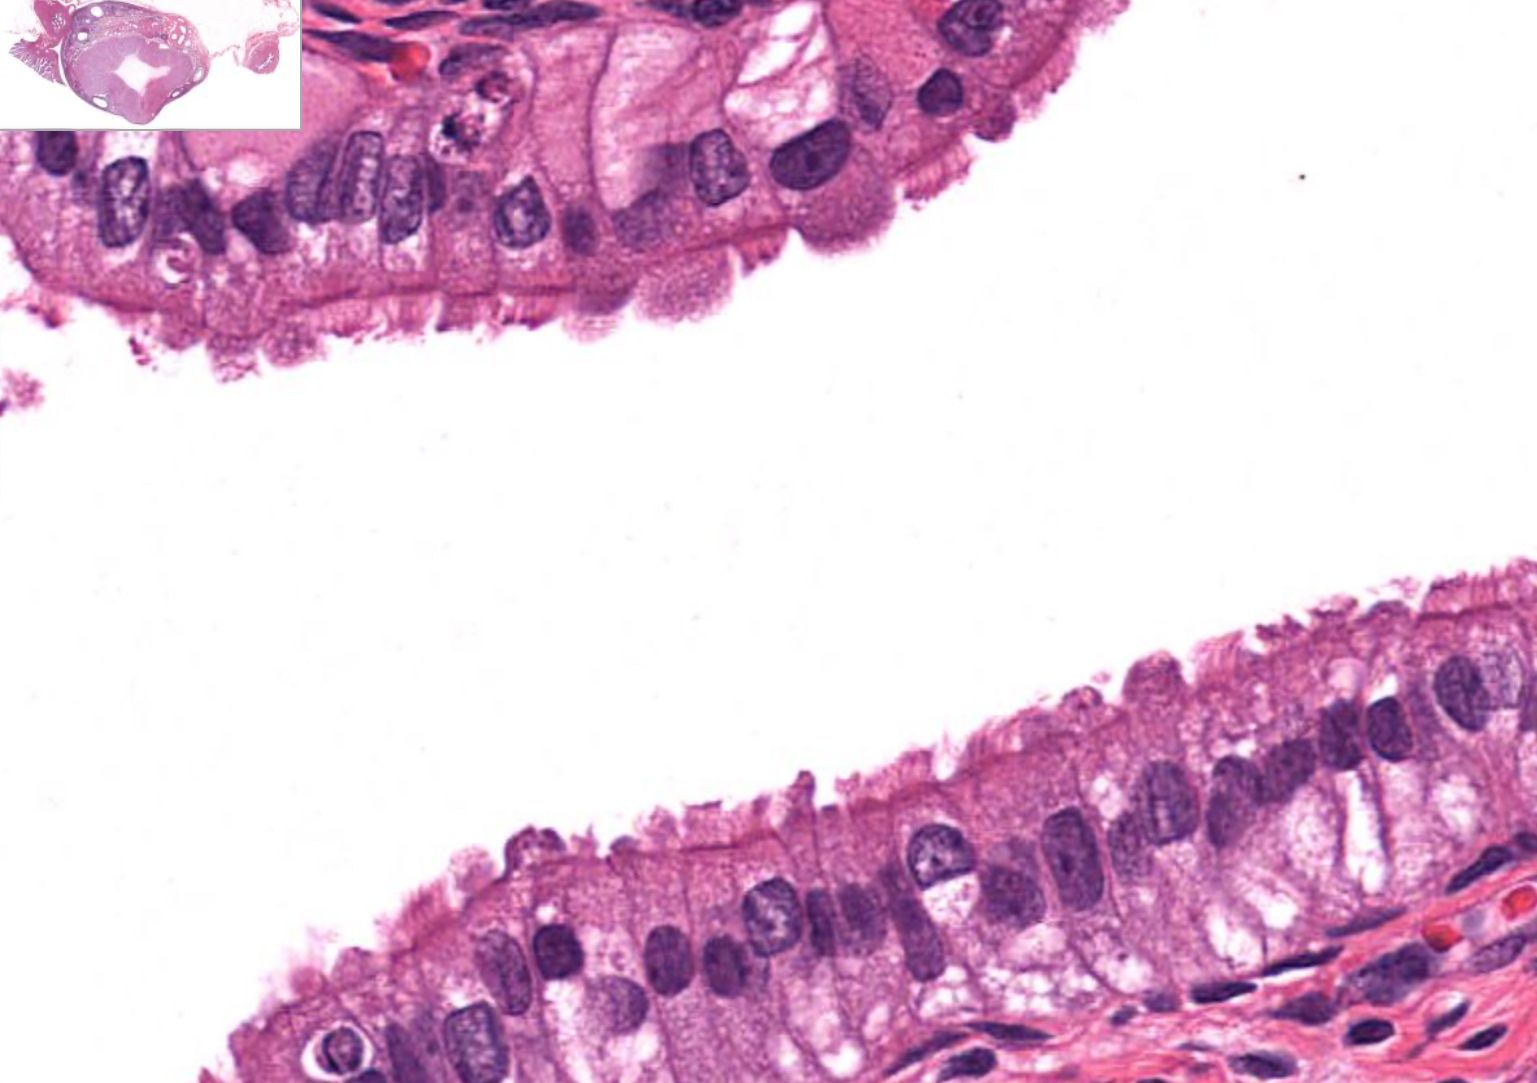

term image

Tissue: relaxed transitional epithelium

Location: Lower Urinary Tract

also in: ureters, urinary bladder, part of urethra

Function:

• stretches and permits distention